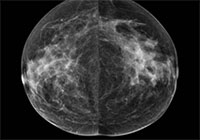

Prior research has shown an association between breast density and breast cancer. In addition, cancers in dense breast tissue are more difficult to see on mammograms. As a result, some women with dense breasts are advised to get supplementary screening with ultrasound or MRI. Some U.S. states have enacted legislation mandating breast density reporting to women undergoing mammography.

Two radiologists read the mammograms independently and determined breast density according to standard criteria. The researchers compared data between patients in the low-density breast tissue group and the high-density group.

The majority of screened woman had low breast density. Of the 230 detected breast cancers, almost half were from the group with the lowest ranked breast density, while slightly less than 3 percent came from women in the highest breast density category.

When the researchers matched the women who had a detected cancer with control participants of the same age and from the same locales who did not have cancer, they found no significant difference in mammographic density. Women with low mammographic density made up 83 percent of the patients in the breast cancer group, compared with 89 percent in the control group, while high mammographic density was found in 17 percent of the breast cancer patients and 11 percent of women in the control group.